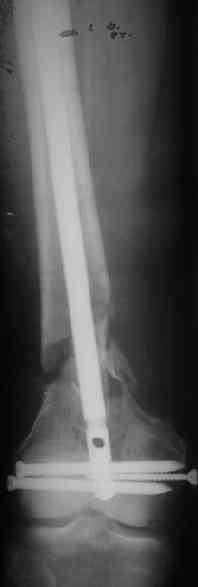

> Хотелось бы узнать какую тактику  лечения Вы предпочли? Речь идет о

> пациенте 60-ти лет с переломом  дистального отдела бедренной кости,

> фиксированного пластиной?

Удалили ластину без проблем. Выявилась значительная подвижность. В

этих условиях сразу пропала мотивация к постепенной коррекции аппаратом.

винт. И сделали антгерадное штифтование, как говорится, "по принятой в

клинике методике".

Длину восстановили, возможно, даже с изьбытком, ну да динамизируем

пораньше. Введенные в овальное отверстие  дистальые винты имеют

угловую стабильность.  Снимки приложены. Заранее спасибо за критику и

комментарии.